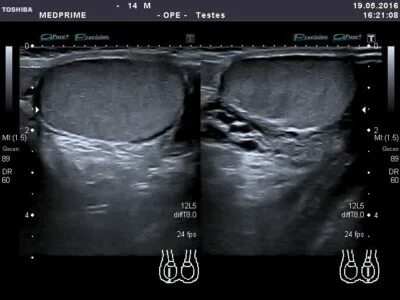

Левое яичко уплотнение